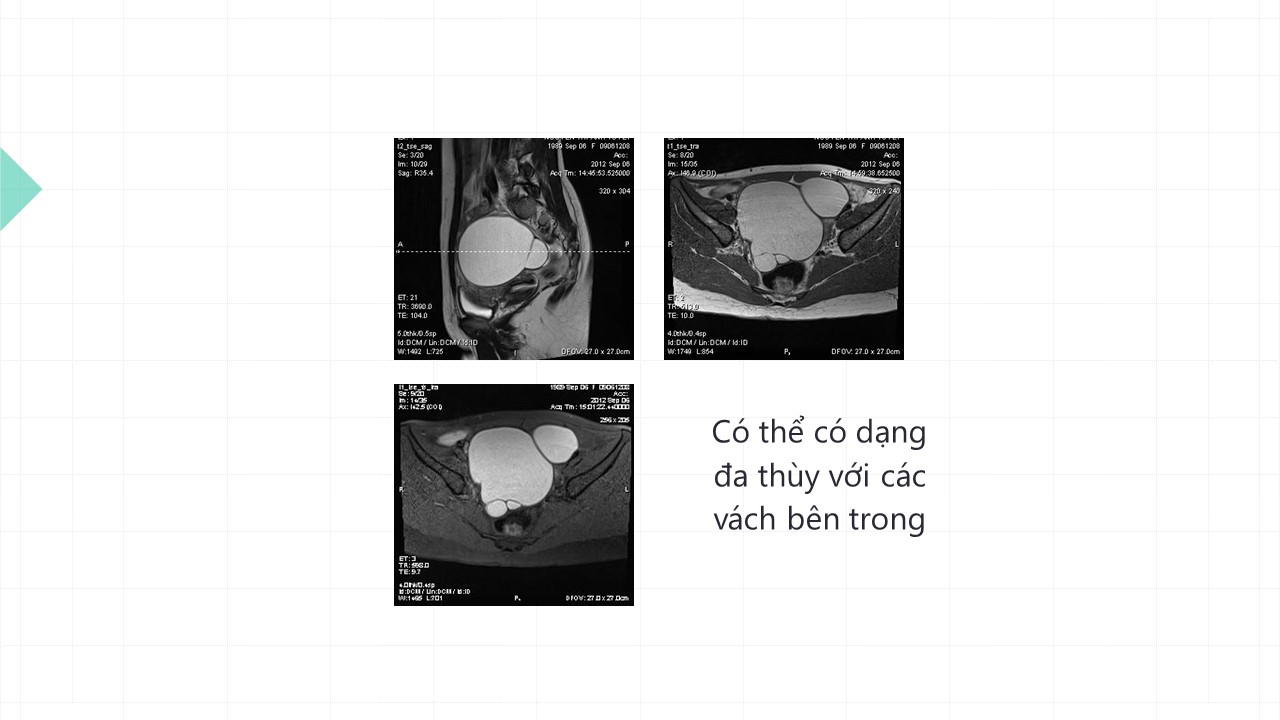

Vai trò cộng hưởng từ trong đánh giá lạc nội mạc tử cung